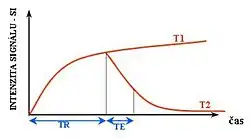

T1 e T2

Cada tecido retorna ao seu estado de equilíbrio após a excitação pelos processos independentes de T1 (spin-tretice) e T2 (spin-spin) de relaxamento. Para criar uma imagem ponderada em T1, a magnetização pode ser recuperada antes de medir o sinal MR, alterando o tempo de repetição (TR). Esta ponderação de imagem é útil para avaliar o córtex cerebral, identificando tecido adiposo, caracterizando lesões focais e, em geral, para obter informações morfológicas, bem como para imagens pós-contraste. Para criar uma imagem ponderada em T2, a magnetização pode decair antes de medir o sinal MR alterando o tempo de eco (TE). Esta ponderação de imagem é útil para detectar edema e inflamação, revelando lesões de substância branca e avaliando a anatomia zonal na próstata e no útero.

Na espectroscopia de RMN é possível controlar a radiação eletromagnética (faixa de radiofrequência ou RF) e descrever a interação desta radiação com os spins nucleares do sistema. Isto contribui em grande parte para o desenvolvimento do grande número de técnicas utilizadas em RMN. Quase todos os elementos químicos têm ao menos um isótopo com um núcleo atômico que possui momento magnético, e quando este é colocado em um campo magnético externo, e a ele for aplicada uma excitação com frequência igual a sua frequência de precessão , tal núcleo é retirado de seu estado de equilíbrio. Após a retirada do campo de RF, este núcleo tende a voltar ao seu estado fundamental de equilíbrio através dos processos de relaxação spin-rede (T1) e relaxação spin-spin (T2)